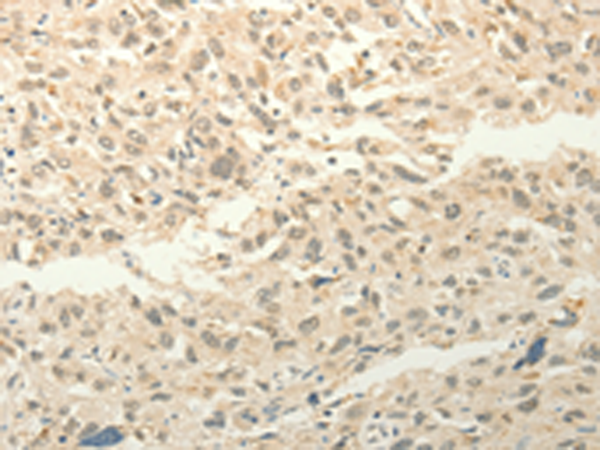

ELISA, IHC |

IHC positive control: |

Human esophagus cancer and Human liver cancer |

IHC Recommend dilution: |

50-200 |